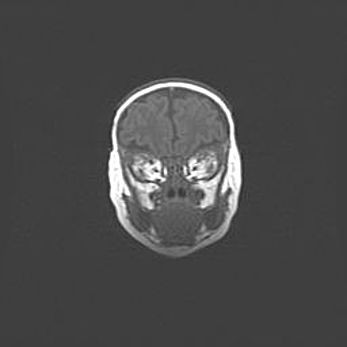

Мальформация Денди-Уокера. Киста задней черепной ямки.

Агенезия мозолистого тела.

Возраст: 2,5 месяца

Вес: 2420 г

Пол: женский

Окружность головы: 37 см

Срок гестации: 32 недели

Мальформация Денди—Уокера — редкий вид патологии ЦНС, представляющий собой врожденный порок развития каудального отдела ствола и червя мозжечка, ведущий к неполному раскрытию срединной (Мажанди) и латеральных (Лушка) апертур IV желудочка мозга. Для этогно синдрома характерна триада симптомов: гипотрофия червя мозжечка и/или полушарий мозжечка, кисты задней черепной ямки, гидроцефалия различной степени. В 70% случаев порок сочетается и с другими аномалиями головного мозга, в частности с агенезией мозолистого тела.